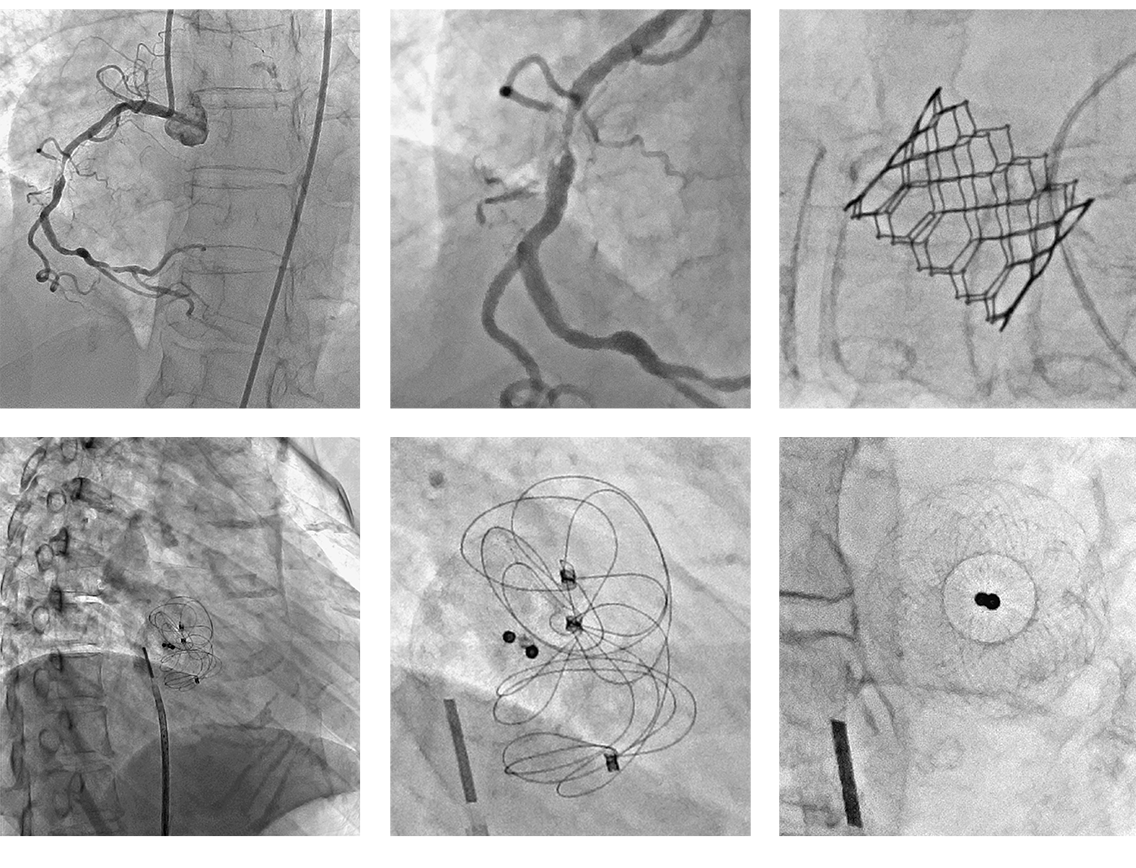

Вишукана детальна візуалізація ураження, структури клапана та оклюдера, отримана за допомогою Hi-Def при FOV 8 х 8 см (3") (посередині та справа) порівняно з FPD 12" (ліворуч) під час різних процедур.

Надано Салманом А. Арейном, доктором медичних наук, FACC, FSCAI, і Річардом Смоллінгом, доктором медичних наук, FACC, MSCAI, Науковий центр охорони здоров’я Техаського університету в Х’юстоні, штат Техас.